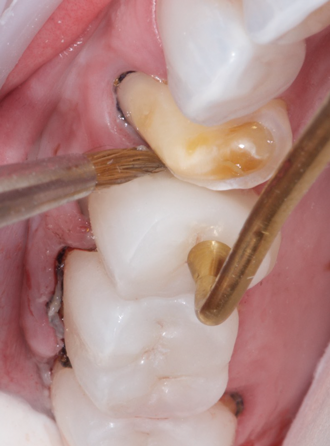

(3.) Prior to placing the restorations, the enamel of the abutment teeth is selectively etched with phosphoric acid for 20 seconds and a self-etch dentin primer is applied.

Figure 3

(4.) Prior to placing the restorations, the enamel of the abutment teeth is selectively etched with phosphoric acid for 20 seconds and a self-etch dentin primer is applied.

Figure 4